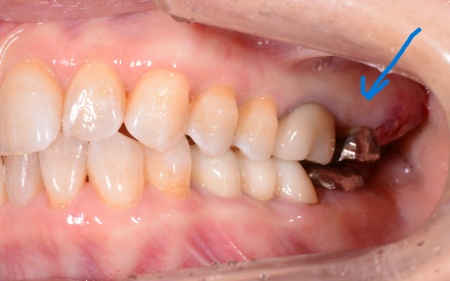

治療前

| 診断結果 | 拝見したところ、左上の一番奥の歯(第2大臼歯)には金属の被せ物が装着されていました。 さらにレントゲン撮影などの検査を行い詳しく確認した結果、歯の根が割れていることが分かりました。 銀歯が被せられている歯は、過去に神経を取る治療を受けているケースが多くあります。 神経を失った歯は時間の経過とともに強度が弱くなり、そこに食いしばりや歯ぎしりなどによる強い噛む力が長期間かかることで、歯の根が割れてしまうことがあります。 今回のように歯の根が割れてしまっている場合、歯を残す治療は困難です。 そのまま放置すると、歯ぐきの炎症が広がったり周囲の歯やあごの骨に影響が出たりする可能性があるため、左上の奥歯は抜歯が必要と診断しました。 |